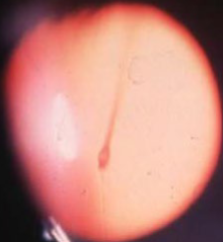

persistent hyaloid artery

congenital

appearance:

short stub of vessel projecting into vitreous

may run forward to lens

single vessel, no return to disc

most are bloodless but some may still have blood

complications:

rare vitreous hemorrhage